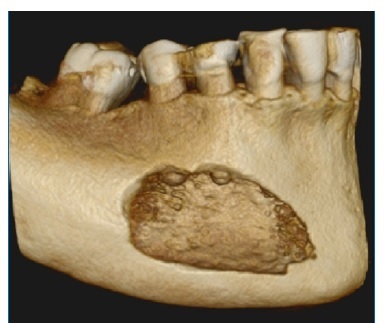

A TC (Figuras 1, 2 e 3) revelou imagem hipodensa, ostelítica, de forma ovalada, promovendo rompimento da cortical vestibular, envolvendo o ápice dos dentes 44 e 45. Nesse momento, a paciente informou ter o diagnóstico de mieloma múltiplo há sete anos, sendo acompanhada por hematologista, sem apresentar sinais clínicos da manifestação da doença.

Figura 1 Reconstrucao axial de TC, evidenciando lesão hipodensa, osteolitica, causando rompimento da cortical vestibular e medindo 19 mm x 25 mm.

Figura 2 Reconstrução parassagital de TC. Observa-se lesão hipodensa e osteolítica envolvendo o ápice do dente 44